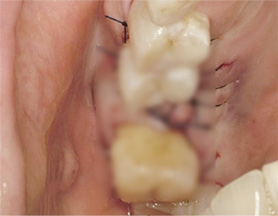

아래턱 어금니 발치 후 장시간 방치하여 잇몸 뼈 소실이 심한 상태로 내원. 뼈 이식 후 임프란트를 식립하였습니다.

잇몸 뼈 소실이 심한 상태로 내원